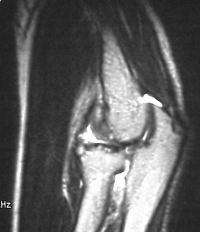

MRI shows an osteochondral sequestrum of the anterior capitellum: